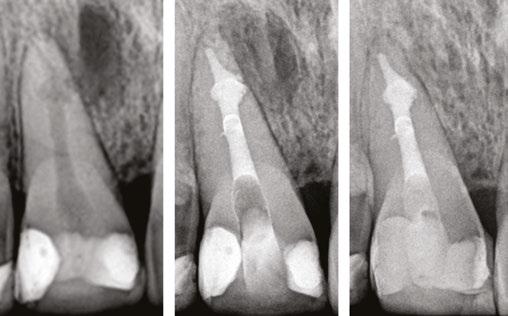

Figures 1A-1C: 1A. Preoperative X-ray. 1B. Immediate postoperative X-ray. 1C. Follow-up after 9 years and 10 months

Of the total, 29 had long-term radiographic follow-ups that ranged from a minimum of 6 months to a maximum of 25 years, with an average of 5 years, 4 months. Of the cases with radiographic follow-ups, 28 were considered successful and one failure (Table 2). Of the successful cases, 17 corresponded to treatments and 11 to retreatments (Figures 1A, 1B, 1C, and 2A, 2B, 2C). The tooth considered failed was a retreatment.

Figures 2A-2C: 2A. Preoperative X-ray. 2B. Immediate postoperative X-ray. 2C. Follow-up after 18 years and 6 months

Figures 3A-3C: 3A. Preoperative X-ray. 3B. Immediate postoperative X-ray. 3C. Follow-up after 4 years